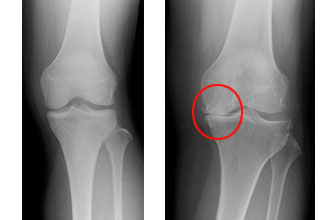

25/4/17 関節内遊離体とは、けがや病気により関節軟骨やその下の骨(軟骨下骨)の一部が剥がれ、膝や肘などの関節内を移動するようになった骨軟 骨片 ( かけら ) のことを指します。 関節内を動き回る関節内遊離体は、俗に「関節ねずみ」とも呼ばれています。 関節内遊離体は、膝や股関節、肘や足首、顎関節など、病気が起こっているさまざまな関節に生じ得12/3/21 関節ねずみとは? 関節ねずみとは、関節内に出来た骨の破片のことを言います。 関節ねずみとは俗称で、正式名称は「関節遊離体」「遊離軟骨」「関節内遊離体」などと呼ばれます。 ただ正式名称が長い上に色々な呼び方がされるので、関節ねずみと呼ばれることの方が多いと思います。病院別 関節内遊離体の治療実績 「 関節内障、関節内遊離体 」の治療実績数を、便宜上"関節内遊離体"のランキングとしています。 この件数には、他の病気の治療も含まれることがあります。 ※件数が10件未満の場合は、統計が公開されていません。 そのため合計数・順位に誤差があることがあります

関節遊離体をそれぞれ3群 に分類すると,表1の 如 く,離 断性骨軟骨炎では,歳 から80歳(平 均35歳)で 12名,骨 軟骨腫症では,31歳 から74歳(平 均51歳)で11 名,い ずれとも判然とせぬもの18歳から66歳(平かんせつゆうりたいかんせつねずみ関節遊離体(関節鼠) Loose Body, Joint Mouse どんな病気か 主として軟骨や骨の小片が、関節内に遊離して動きまわるものを、関節遊離体あるいは関節鼠といいます。 このようなことがおこる原因としては、離断性骨軟骨炎(りだんせいこつなんこつえん)、骨軟骨腫症(こつなんこつしゅしょう)、骨軟骨骨折などがありますが関節遊離体 カンセツユウリタイ 関節遊離体はどんな病気? 関節遊離体とは、関節の中にはく離した骨が存在する状態を指す言葉です。 別の呼び方としては、関節ねずみなどと言うことがあります。 これは、いろいろな関節で発生する可能性があります。 一般的には、指やひじなどの関節に多く見られると考えられています。 これが発生する原因として

ブログ 膝離断性骨軟骨炎 しつりだんせいこつなんこつえん 熊本の弁護士 交通事故のトラブル弁護は田中ひろし法律事務所